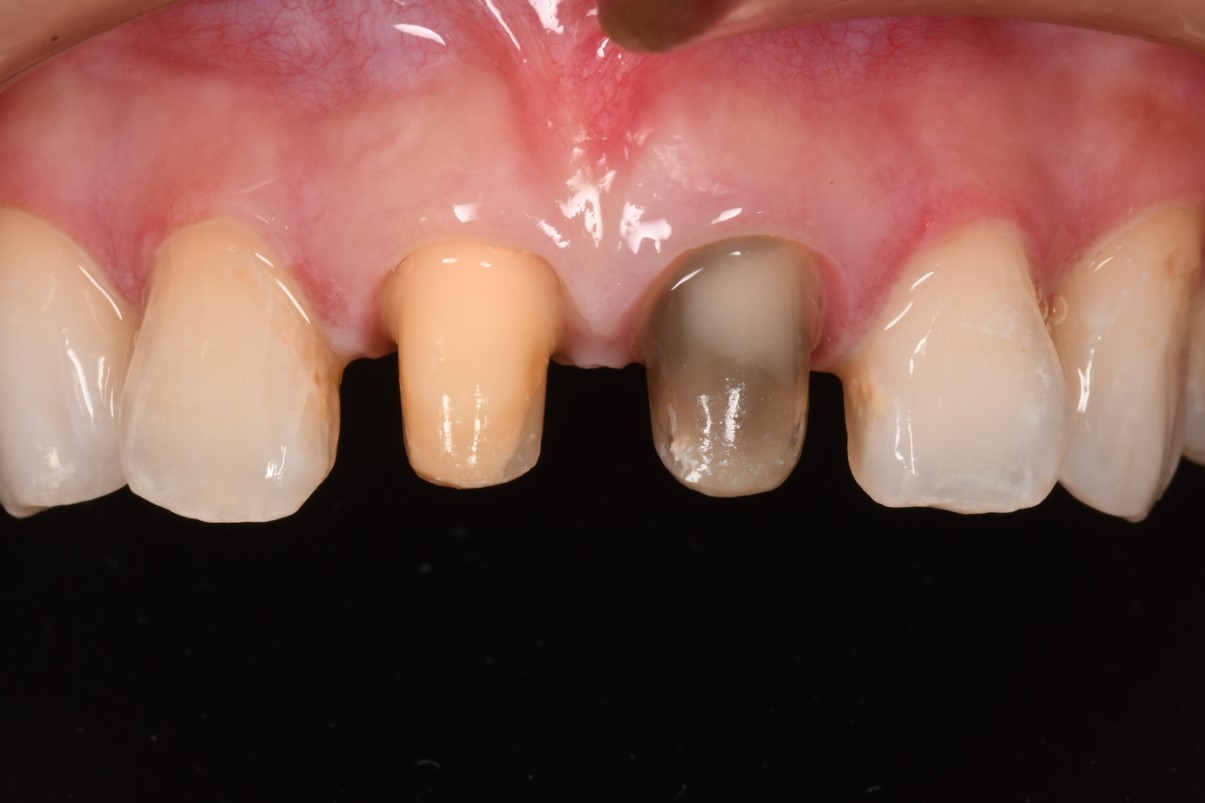

先更換上顎門牙臨時假牙

膺復前評估